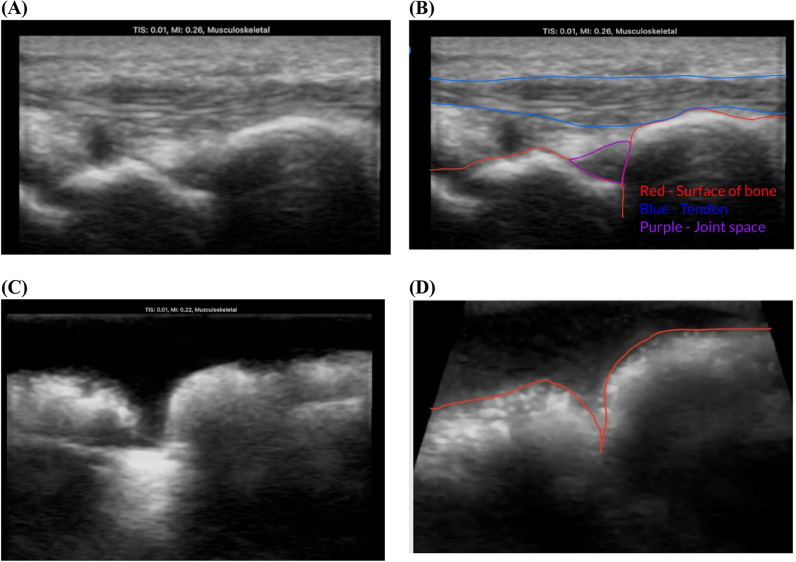

Results: We developed a novel ultrasound compatible wrist joint model that can be made from sustainable materials and reusable parts, thus reducing the costs for acquisition and environmental impact. Our model, which was produced utilizing small-batch production methods, is made up of 3D-printed bones enclosed in an ultrasound-compatible gelatin mixture. It can be easily remade after each practice session, removing needle tracks that are visible under ultrasound for conventional phantoms. The ultrasonic properties of this model were tested through pixel brightness analysis and visual inspection of simulated anatomical structures.